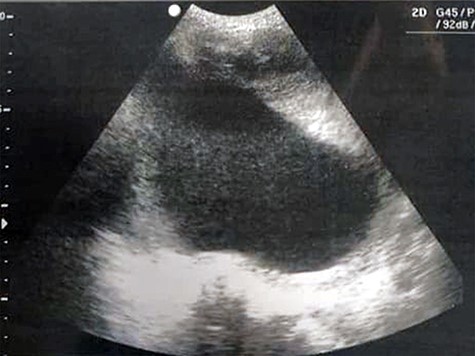

A 51-year-old woman (G 17, P 15, Ab 2) presented to the emergency department with low abdominal pain. Her gynecological history reveals pelvic pressure, irregular menstruation and menorrhagia during the past 3 months. She stated that all her pregnancies were delivered vaginally. Otherwise, neither her medical, surgical nor familial history was significant. At admission, her vital signs were in the normal range, she had mild pallor, she was afebrile and did not complain of nausea or vomiting. Her physical examination showed abdominal distention, enlarged uterine, equals to 20 weeks’ gestation. The remaining of her systemic examination was unremarkable. The patient’s laboratory tests showed microcytic anemia [RBCs: 4.42 × 106/ul, Hb: 11.2 g/dl, Hematocrit: 31.5%, MCV: 71.2 fl] and a slight increase in platelets count [403 × 103/ul] with normal white blood cell count. Her liver and kidney function were sufficient. Normal CA-125 and alpha-fetoprotein levels excluded any concerns about sarcomatous changes in leiomyoma; we were unable to perform the MRI and isoenzyme testing because they are high-priced investigations. Beta-hCG levels were normal, which exclude ectopic pregnancy. Doppler ultrasound was unavailable in our department; hence, we used normal ultrasound to rule torsion or rupture of any ovarian cysts. Both transvaginal and transabdominal ultrasound showed a large heterogeneous mass in uterine wall (Fig. 1). Pelvic CT scan reported an irregular mass measures 20 × 17 cm with central necrosis (Fig. 2).

Transvaginal ultrasound showing a heterogeneous mass in the uterinewall.